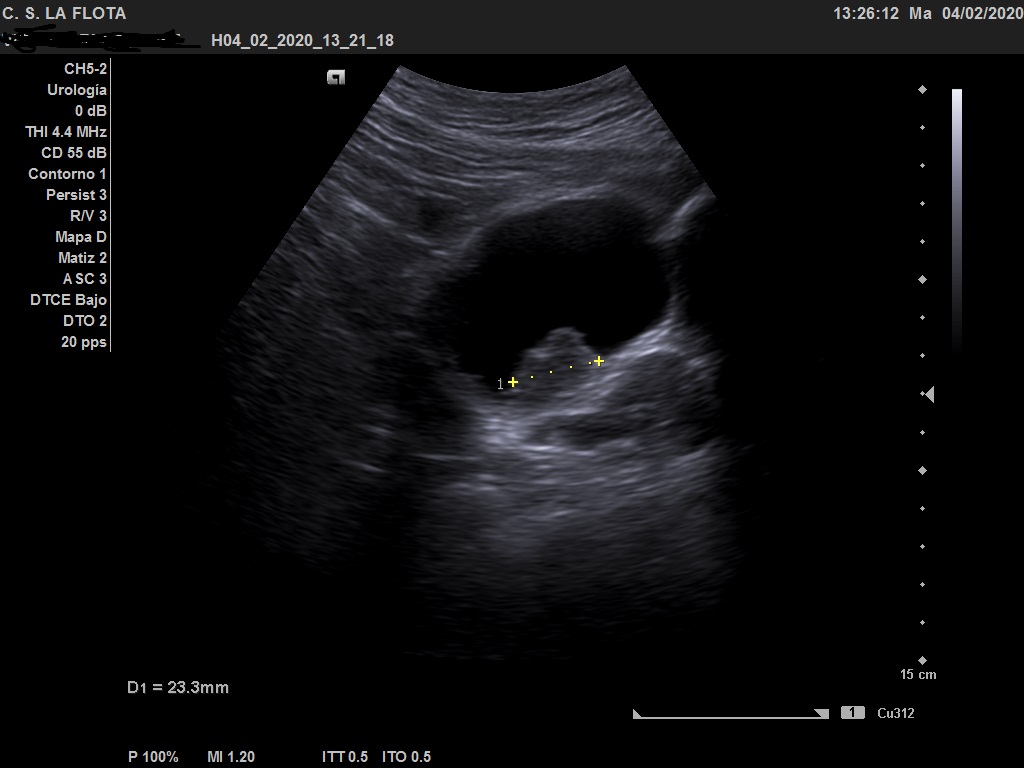

Ecografía clínica: riñones de tamaño y morfología normal, con buena diferenciación corticomedular y sin dilatacion de vias. En vejiga lesión polipoidea  de 25*18 mml.

Ante los hallazgos ecográficos se derivó al paciente a urología con copia de las imágenes. En urología solicitan cistoscopia sin precisar más pruebas de imagen.